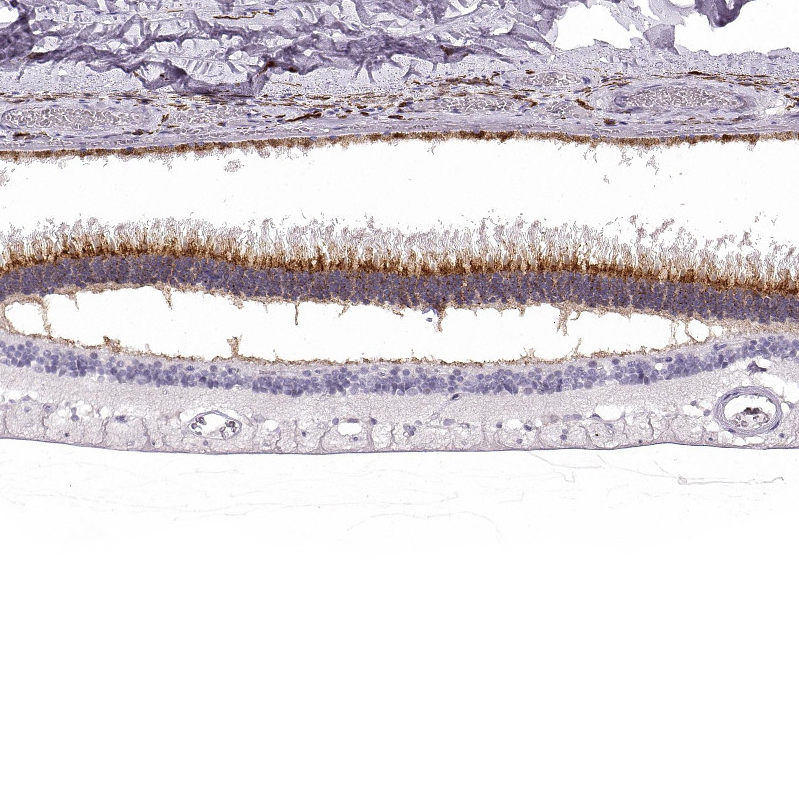

Immunohistochemical staining of human cerebral cortex, eye, retina, liver and skeletal muscle using Anti-IMPG1 antibody HPA027142 (A) shows similar protein distribution across tissues to independent antibody HPA030332 (B).